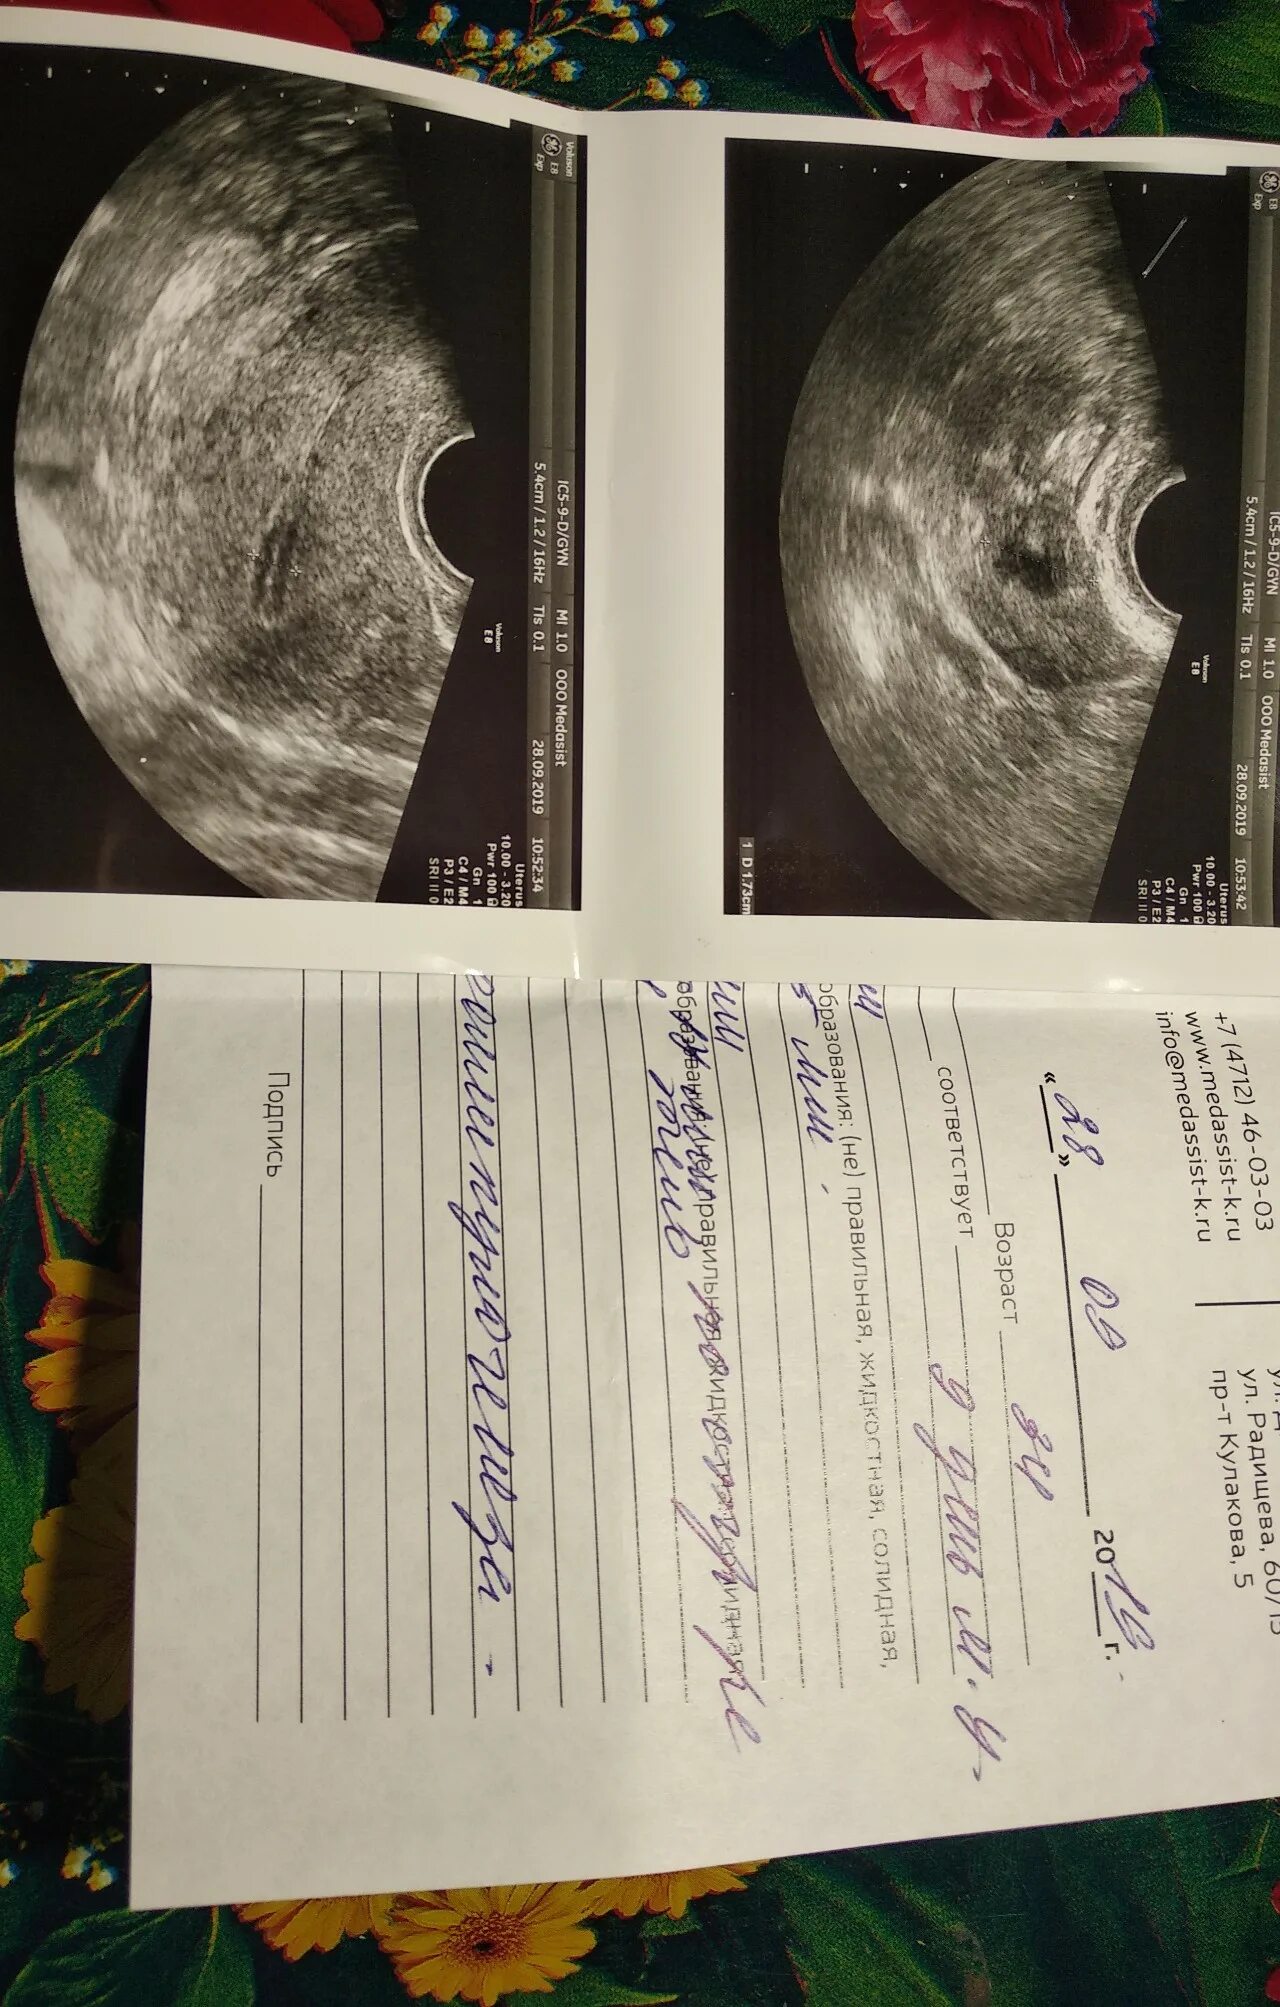

Узи овуляции как называется